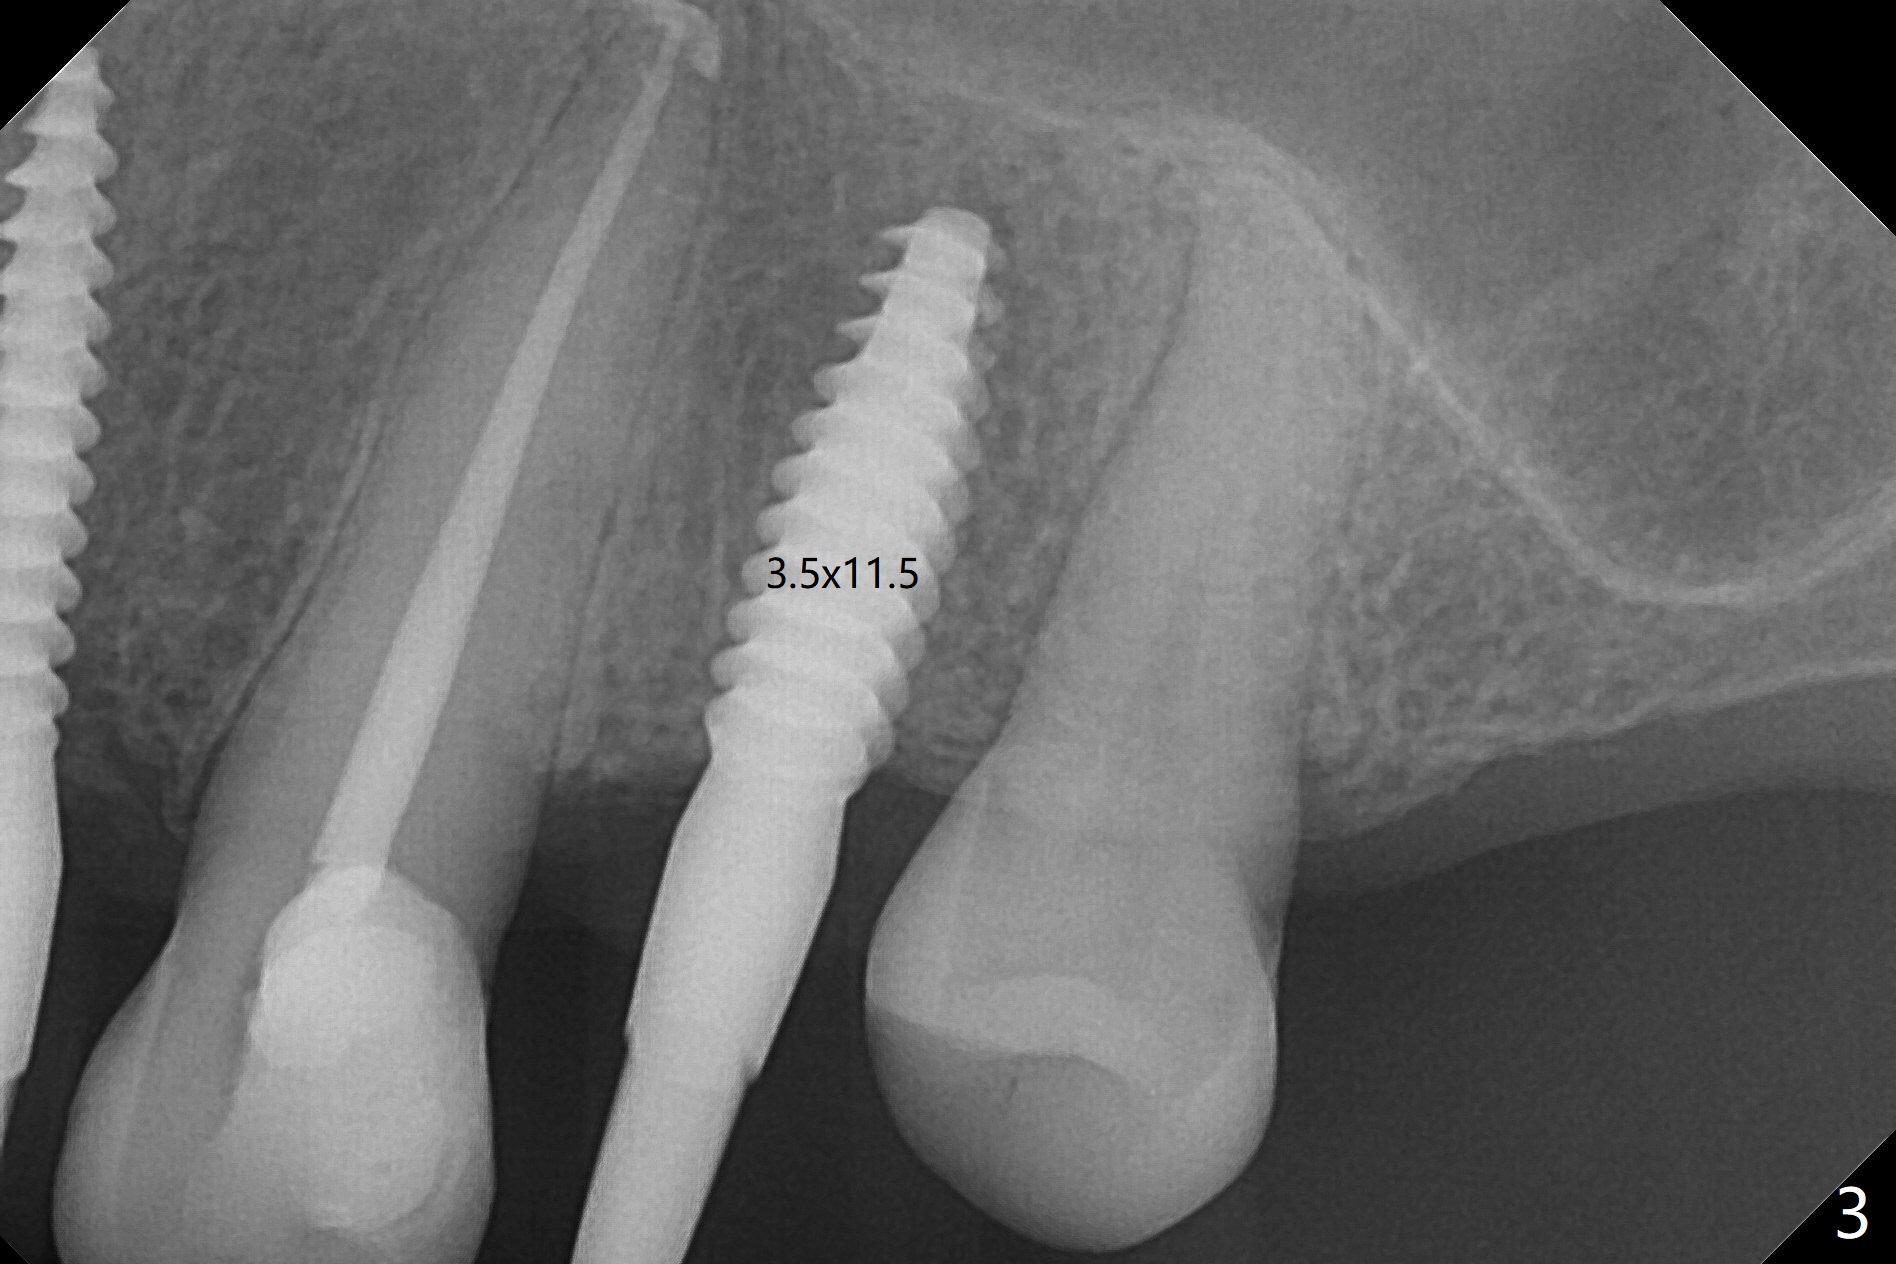

After removal of #10 sleeve and 3 spot adjustment, the guide is seated without satisfaction. When the guide is removed after pointed drill, the osteotomy seems distal (Fig.1). Incision is made with flap elevation for free hand osteotomy. A 1/1.6 mm bone expander is inserted after 1.2 mm drill, the trajectory appears to be right (Fig.2). As the osteotomy increases in diameter, the buccal plate feels to be vibratory. A 3.5x11.5 mm 1-piece implant placed initially is apparently away the sinus floor (Fig.3). Further placement (subcrestal, Fig.4) seems to be associated with more buccal plate perforation (Fig.6 *), which is repaired by bone graft. Since the implant at #10 appears to be doing okay 1.5 months postop (Fig.5), the implant at #12 is not removed immediately. A tunnel incision will be made for bone graft in the most apical concave areas (Fig.7). The osteotomy should have been made more palatal to reduce the chance of the buccal perforation. CBCT should have been taken while the 1/1.6 bone expander was in place.